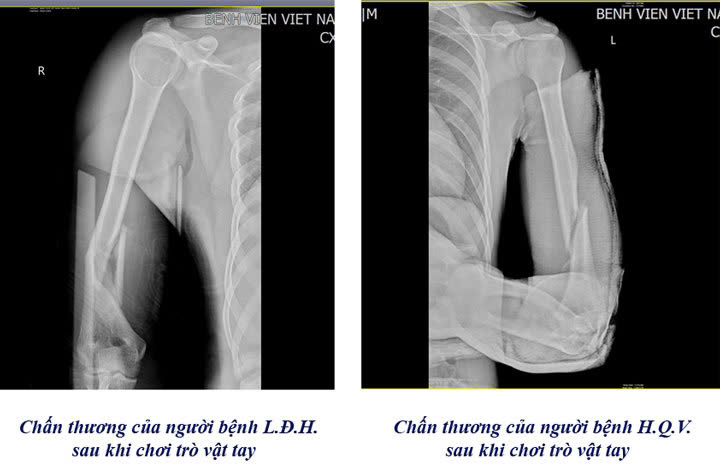

Cảnh báo nguy cơ gãy tay từ trò chơi vật tay

Chỉ trong vòng 1 tuần, Khoa Chấn thương Chỉnh hình & Bỏng, Bệnh viện Việt Nam – Thụy Điển Uông Bí đã tiếp nhận 3 trường hợp nhập viện do gãy xương cánh tay, nguyên nhân là từ trò chơi “vật tay”.

Theo bác sĩ Khoa Chấn thương Chỉnh hình & Bỏng cho biết: khi vật tay, lực xoay đột ngột tác động lên xương cánh tay có thể vượt ngưỡng chịu đựng, gây gãy xoắn xương cánh tay, thậm chí di lệch. Các trường hợp này thường phải tiến hành phẫu thuật kết hợp xương bằng nẹp vít. Đây là kỹ thuật hiện đại và phổ biến trong điều trị gãy xương cánh tay, mang lại hiệu quả cao giúp người bệnh gãy xương mau lành, cố định vững chắc vị trí gãy và tạo điều kiện thuận lợi cho quá trình liền xương.

Cũng theo bác sĩ, bệnh viện thường xuyên tiếp nhận các trường hợp bị gãy xương cánh tay từ trò chơi “vật tay”. Có những trường hợp nhập viện trong tình trạng gãy nham nhở, gây khó khăn cho các bác sĩ trong việc đưa các mảnh xương về vị trí ban đầu, gia tăng nguy cơ tổn thương dây thần kinh quay, dây thần kinh trụ và mạch máu lân cận. Đa phần các trường hợp nhập viện đều ở độ tuổi học sinh, sinh viên.

Các bác sĩ khuyến cáo phụ huynh và nhà trường cần tuyên truyền, nhắc nhở học sinh, sinh viên không tham gia trò vật tay. Người lớn cũng cần tránh thực hiện khi không nắm được kỹ thuật, chỉ 1 chút sai sót cũng có thể khiến bạn bị ảnh hưởng về sức khỏe. Khi xảy ra tai nạn, cần cố định tạm thời cánh tay, không tự nắn chỉnh, nhanh chóng đưa người bệnh đến cơ sở y tế gần nhất để điều trị.